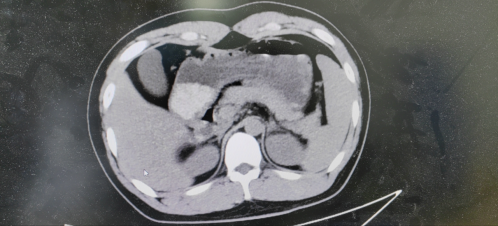

很快,上腹部CT检查提示:胃部呈高密度影,结合病史症状,临床高度怀疑口服镇静催眠药物的可能。遂在应用药物稳定血压与呼吸的同时,给予洗胃治疗,现场洗出大量绿色液体,洗胃后紧急收治急诊病房。

*胃部高密度影